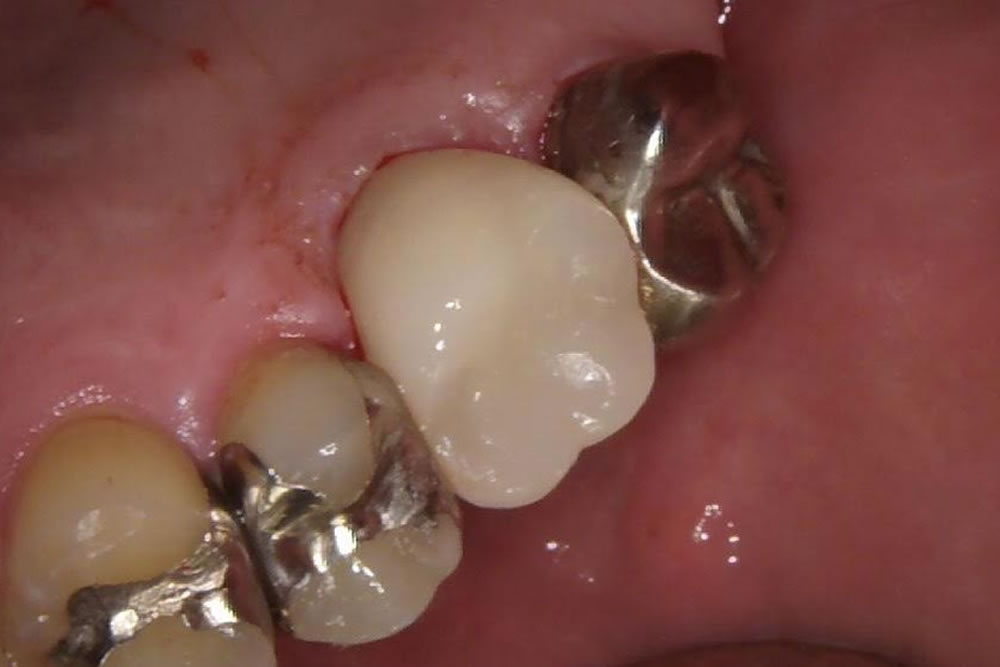

段差が気になる銀歯をセラミックで改善した症例

こちらの患者さまは銀歯に段差ができているのが気になるとの主訴で来院されました。まずは銀歯を除去し、中に入っている金属の土台も除去していきます。

かぶせ物については、虫歯になるリスクの低いセラミックにて作成していきたいというご希望でしたので、中にファイバーの土台を作成し、セラミッククラウンを装着しました。

結果見た目も綺麗になり、今後虫歯になりにくくする事ができました。